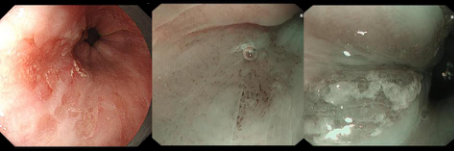

在科室何林方主任的带领下,科室常规开展无痛胃肠镜、精查染色胃肠镜、超声胃肠镜、色素放大内镜、窄带成像技术(NBI)、磁控胶囊胃镜、胶囊小肠镜等检查,能开展胰胆疾病的内镜下治疗(ERCP):包括十二指肠乳头肌切开(EST)、胆管取石术、胰胆管支架置入术、内镜下鼻胆管引流术;食管胃底静脉曲张套扎、硬化剂、组织胶注射治疗;内镜下的粘膜剥离术(ESD)、内镜黏膜下切除术(EMR)、经口内镜食管括约肌切开术(POME)、经内镜黏膜下隧道肿瘤切除术(STER)、空肠管置入术;痔硬化、套扎治疗;胃造瘘(PEG)、食管、肠道支架置入;食管狭窄扩张术,食管瘘口封堵术;经颈静脉肝内门-体分流术(TIPS)、超声内镜引导下的胃曲张静脉精准断流术(EUS-SVD)、内镜超声引导下胆道引流术(EUS-BD)、内镜下幽门括约肌切开术(G-POME)、经内镜逆行阑尾炎治疗术(ERAT)等国际最新内窥镜微创治疗。